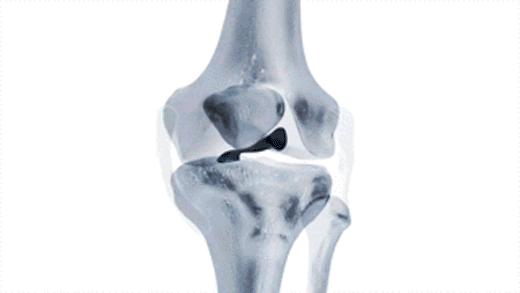

关节内游离体,也叫关节鼠

常见的导致关节内存在游离体的病因,多数是由于关节受到外伤以后,关节腔的软骨脱落到了关节腔内,有的时候这些脱落的软骨会慢慢的被磨损吸收掉,而有的时候这些软骨会慢慢变成钙化形成游离体。(下图就是软骨破裂的影像学资料)

另外还有一种比较常见的情况是关节腔的滑膜软骨瘤病,这种情况就类似于患者的关节腔内滑膜变成了一个巢穴,从巢穴内不停地往关节腔内生产软骨样的游离体。(下图为滑膜软骨瘤病的影像学资料)

由于这些游离体在关节腔内,会发生位置的变化,所以也被称之为关节鼠,有的时候这些游离体会卡别在关节腔内,造成患者出现打软腿的症状,如果卡别的比较急骤的时候,患者就会出现明显的疼痛。

一般情况下,关节腔内游离体的诊断,进行膝关节x线检查就可以明确了。(下图在膝关节后方的都是游离体)